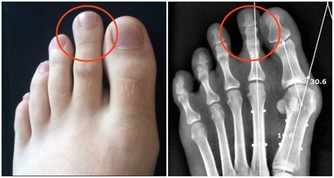

3、保護肺部,遠離肺癌。

有研究顯示,30歲以前戒菸能使肺癌的風險降低90%,戒菸5年後,

由於吸煙所致的口腔和食管腫瘤風險也會降低一半。

多吃堅果。堅果富含元素硒,尤其是開心果。

開心果中的維E也可以保護肺部,降低患肺癌的風險。